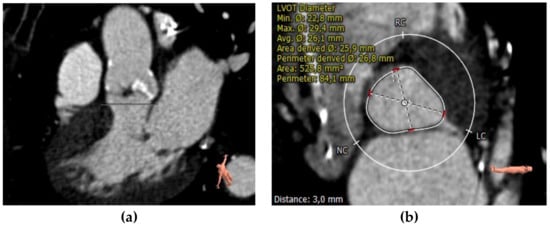

Annular dimension can be quantified with multiple methods: cubic spline interpolation, polygon, attenuation/Hounsfield-unit-based contour detection, and freehand contour. ECG-synchronized, ideally multiphasic, dataset should be used for proper measurement, identifying the reconstruction phase with the largest annular dimensions, thus ensuring accurate device sizing [24]. MDCT sizes the aortic annulus using annular area and perimeter measurements. In the Pivotal Trial of Medtronic Corevalve and the PARTNER 3 trial, it was demonstrated that annulus sizing based on CT measurements reduces the risk of complications such as paravalvular leakages. Moreover, the aortic annulus perimeter or cross-sectional area is superior to the annulus diameter for reducing the likelihood of paravalvular aortic regurgitation (PAR) [37,38] (Figure 3).

Figure 3.

CT measurements of perimeter and area of aortic annulus.

Another goal of current CT sizing algorithms is to calculate a certain degree of oversizing of the transcatheter heart valve (THV) to avoid the post-implantation occurrence of paravalvular leaks (PVLs). It depends on the type of THV and the measurement used (perimeter/area). Self-expandable devices need more oversizing than balloon-expandable prostheses. Conversely, severe oversizing using balloon-expandable devices might increase the annular damage. Additionally, a 10 per cent perimeter oversize does not equal a 10 per cent area oversize, but it is closer to 20 per cent [39].